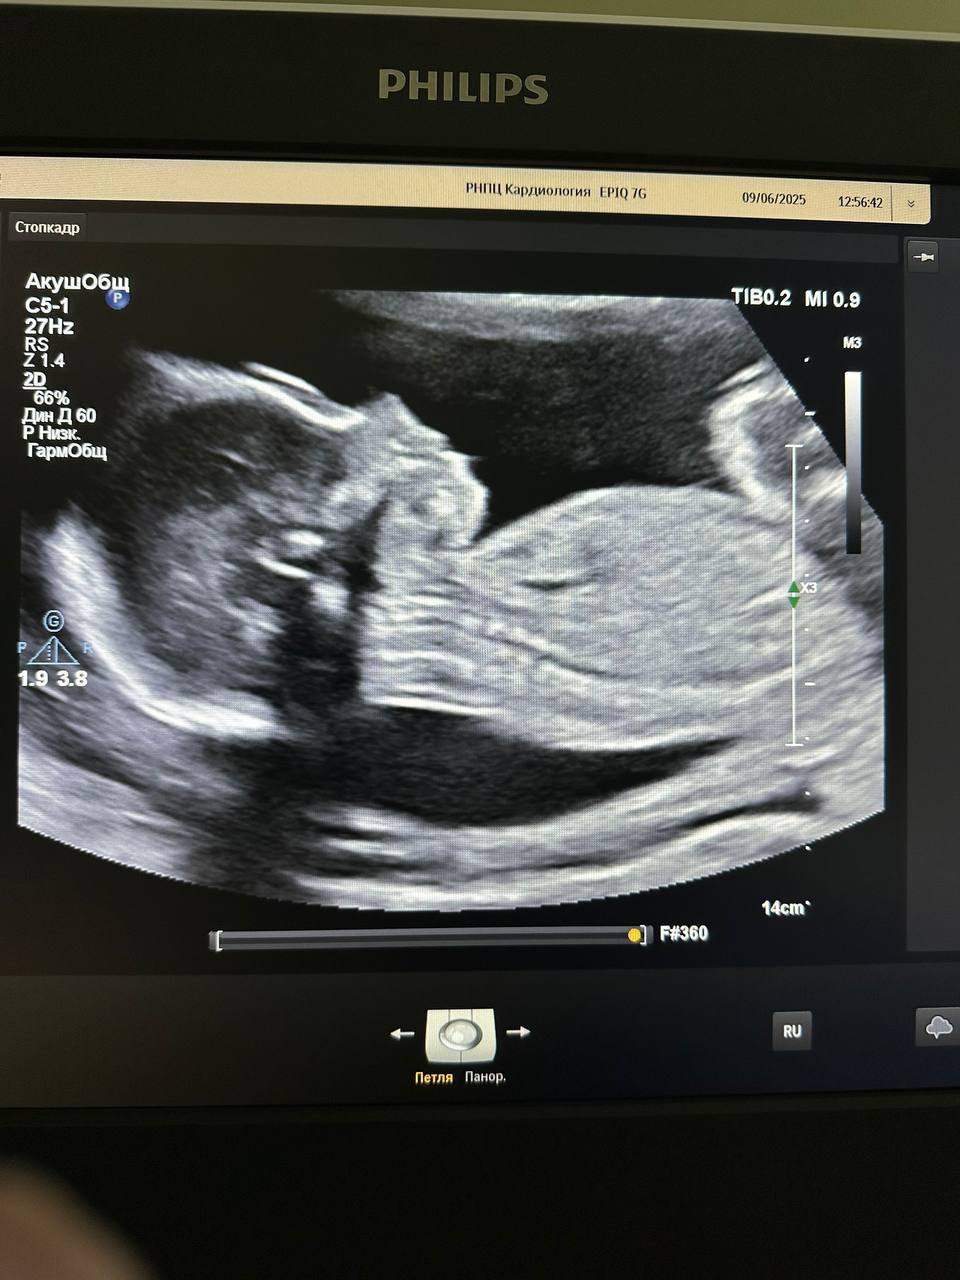

Пациентке 33 года, и в момент хирургического вмешательства женщина была на 23-й недели беременности. Несмотря на положение белоруски, операцию решили не откладывать.

Во время хирургического вмешательства женщина находилась на искусственном кровообращении. Удаление миксомы левого предсердия (доброкачественная опухоль) проходило с применением высокотехнологичного оборудования.

"Операция и послеоперационный период прошли без осложнений. Беременность удалось пролонгировать [продлить] до 38 недель", – рассказали в медучреждении.

Так, 2 октября родился доношенный мальчик весом 3230 г и ростом 52 см. Роды были искусственными: в результате планового кесарева сечения. По шкале Апгар (дыхание, быстрота реакции, сердечный ритм, тонус мышц и так далее) у ребенка удовлетворительные показатели. Он здоров.